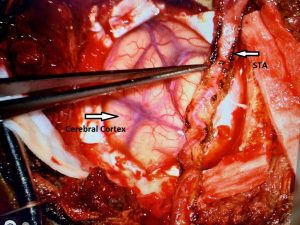

Figure 3

A right sided Encephaloduroarteriosynagios (EDAS) procedure was undertaken in which the right superficial temporal artery (STA) is sewn (synangiosed) to the pia in an effort to generate vascular arborization and increased blood flow to the hemisphere (Figure 3).